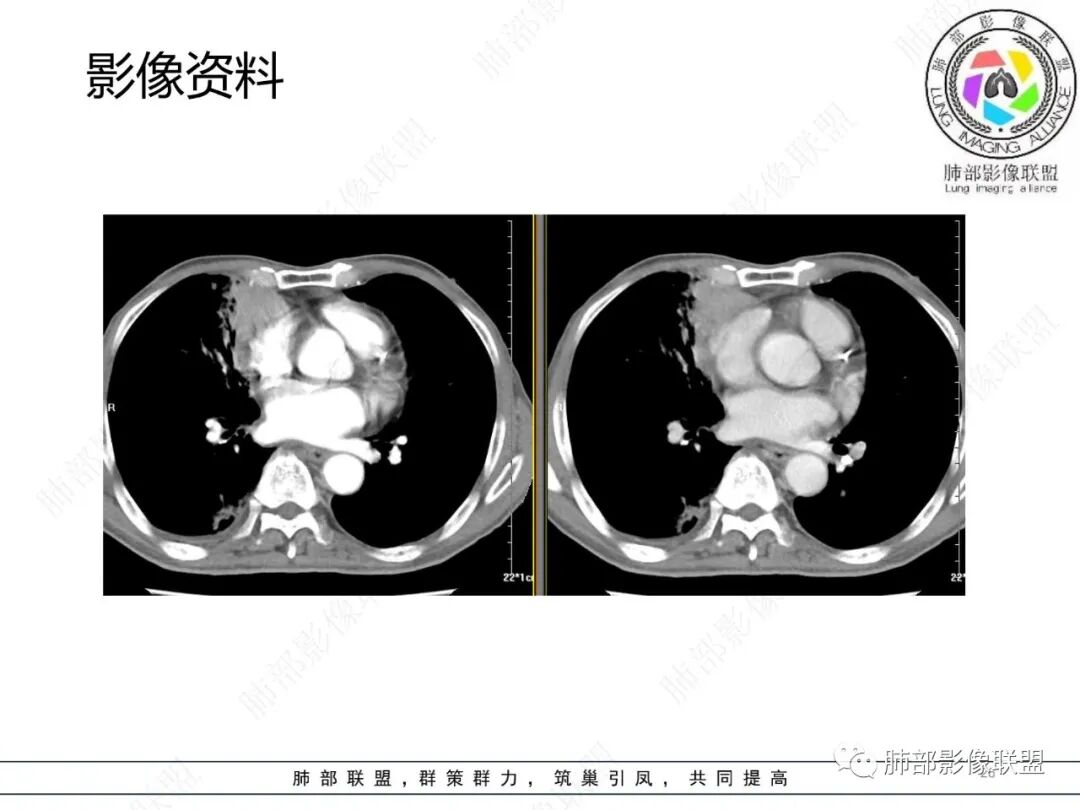

影像资料

2.胸部CT: 右肺病灶,主要累及右肺上叶前段、右肺中叶内侧段及右肺下叶背段,片状影及结节影,实性密度为主,部分磨玻璃晕,密度不均,散在钙化,其中上叶前段支气管闭塞,隐约见钙化突入。未见明确“硬树芽”或“拐枣征”。主要呈延迟强化,其间低密度区疑坏死或粘液成分。纵隔内见多组淋巴结肿大环形强化,部分钙化。

临床免疫缺陷患者呼吸系统症状易想到肺孢子菌或马尔尼菲篮状菌感染。影像不支持肺孢子菌肺炎。马尔尼菲篮状菌肺部感染影像表现多样,可以磨玻璃影、实变影,有时多发结节影酷似继发性肺结核,纵隔或远处淋巴结肿大并环形强化等须仔细甄别。有文献报道马尔尼菲篮状菌肺部感染患者82.7%胸部CT有异常改变,胸部CT表现:45.6%患者肺野斑片状浸润阴影或局限性肺实变,11.9%患者表现为结节影,11.5%患者表现为毛玻璃改变,8.4%患者表现为弥漫性粟粒样病变,5.3%患者表现为结节状肿块影。45.1%患者胸部影像学伴肺门或纵隔淋巴结肿大,23.5%患者伴胸腔积液,8.0%伴空洞病灶。